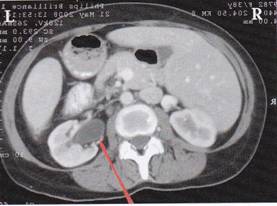

A mellékelt felvételen az alacsony cukorközpontban láthatjuk a Hameri gócot (= „ellenszegülés-konfliktus” a balkezes nő esetében), mely 17 éves korában keletkezett a parkban, amikor szexuális (orális) erőszakot követtek el ellene. Egészen tavalyig még farkaséhsége volt.

Ehhez az „ellenszegülés-konfliktus”-hoz kapcsolódik a „HIV-smegma-konfliktus” (= smegma-allergia).

4.ábra: Tisztán kivehető az alacsony cukorközpontban található Hameri góc („undor/félelem-konfliktus), mely az orális nemi erőszak során keletkezett.

A középső, jobb oldali koponyagödörben található az „esés-konfliktus” során keletkezett Hameri góc (amikor megütötte a fejét az ugródeszkába az uszodában). A kettő között látható a jobb vesegyűjtőcsatorna reléjén fekvő Hameri góc („lét-konfliktus”, oliguria).

A jobb (látszólag nem feltűnő) vese az, amely reléjén az aktív Hameri Góc becsapódott és amelyik visszatartja a folyadékot (oliguria). Ez esetben egy „lét-konfliktus” áll fenn, mert a páciens most egy nigériai férfivel él együtt, akitől egy újabb gyermeke született. Létminimumon él, míg azelőtt megengedhette magának, hogy szórja a pénzt.

A bal vesének (l. nyíl) ún. tágult vesemedencéje van, ez a bizonyíték arra, hogy ott már lezajlott egy vesegyűjtőcsatorna-tuberkulózis folyamat.

Ezeken az ábrákon ugyanaz a bal oldali tágult vesemedence látható horizontális metszetben.